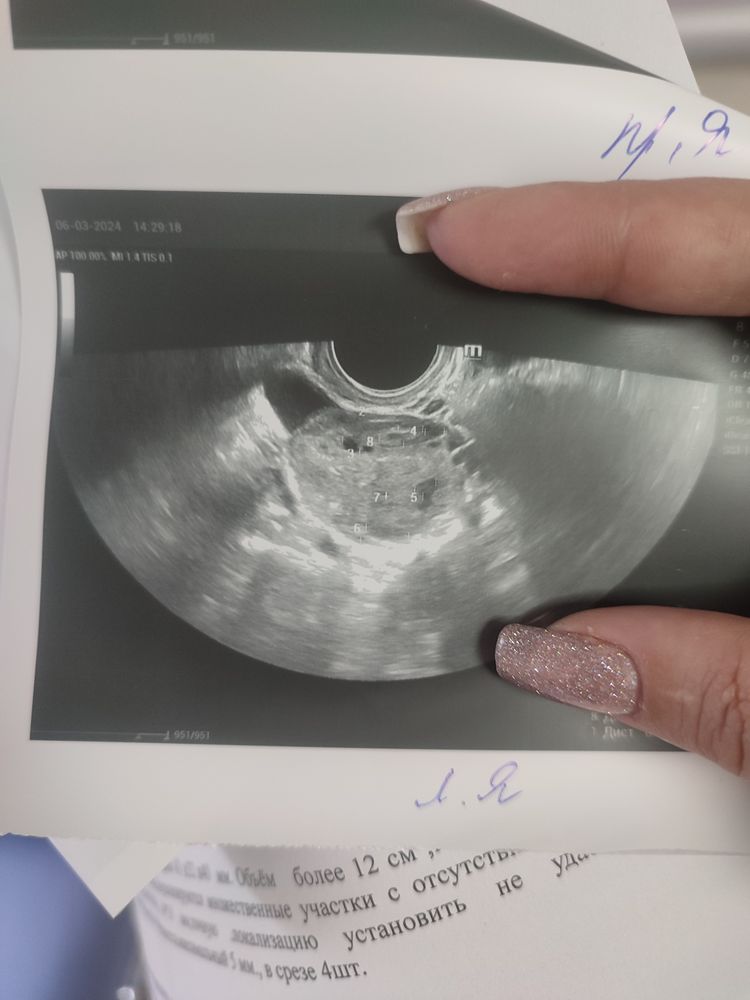

Это_Катя, это понятно просто напряет что левый яичник увеличен при том что фолликулы 5 мм и болит так будто там киста какая то

Кулакова Александра, от стимуляции может быть увеличены, М у меня тоже долго не приходили